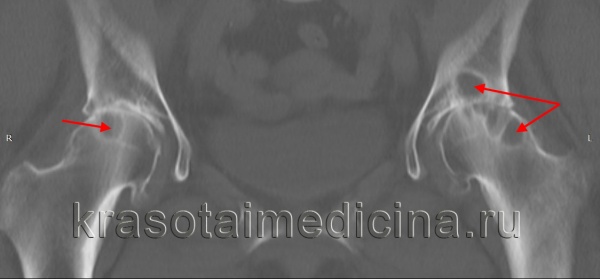

КТ тазобедренных суставов показывает множественные кистовидные участки остеонекроза в головке обеих бедренных костей и в подвздошной кости слева.